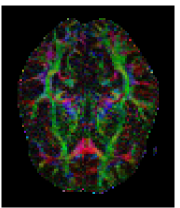

The first eigenvector , also called principal diffusion vector, of describes the predominant diffusion direction, which is parallel to the orientation of the corresponding underlying WM fiber system. Figure 3 shows a visualization of the color-coded MR-DTI data with ellipsoids. The predominant diffusion direction can be directly related to a Green (G), Red (R) and Blue (B) digital color triple. The convention in which the G, R and B color components represent the directions is as follows:

| (6) |

The RGB color-coded directionality maps provide an indication of the direction in which water diffusion is the highest and improve the visibility of different WM fiber bundles.